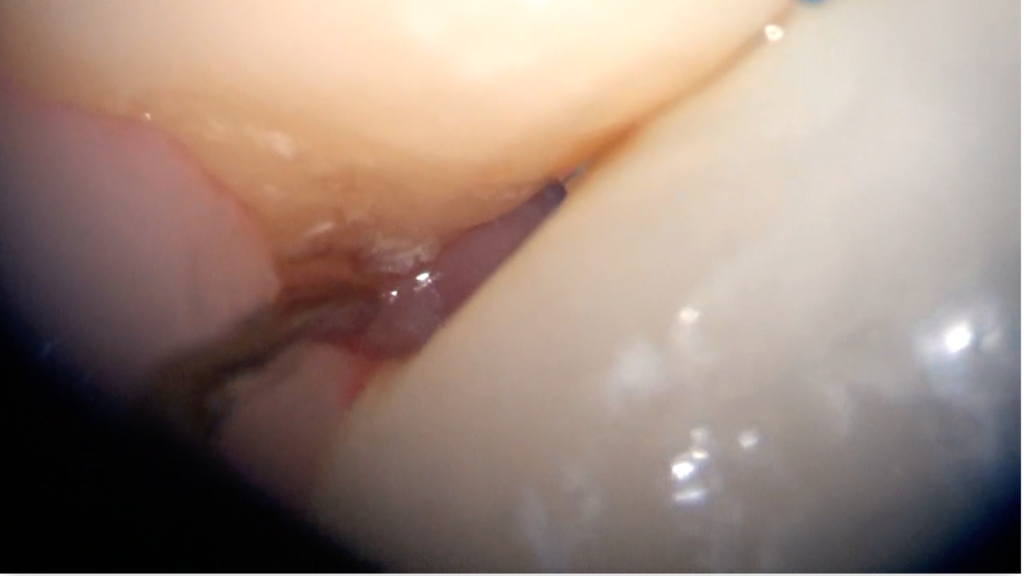

顕微鏡(マイクロスコープ)で歯石を取るメリット

① 圧倒的な視認性(最大20倍前後)

歯科用顕微鏡を使うと、

歯石の位置

大きさ

形状

歯根の凹凸

を直接目で確認しながら処置できます。

これは「感覚」ではなく「視覚」に基づい…